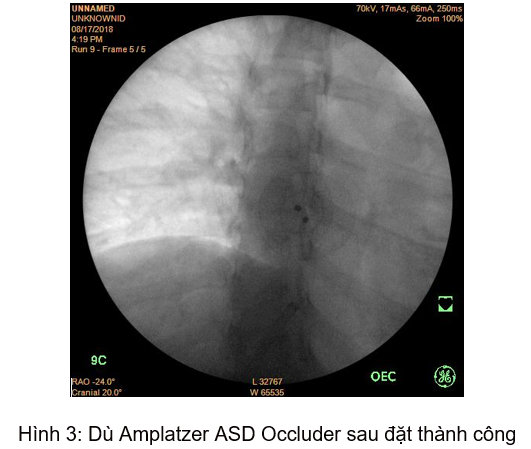

Xác định đây là nguyên nhân gây ra các triệu chứng trên bệnh nhân cũng như khảo sát kỹ cho thấy hình thái cấu trúc, chức năng tim phù hợp, bệnh nhân đã được chỉ định điều trị bằng phương pháp đóng lỗ thông liên nhĩ bằng dù Amplatzer ASD Occluder đường kính 18 mm qua da bằng dụng cụ dưới hướng dẫn của hệ thống tăng sáng số hóa xóa nền và siêu âm tim doppler màu.

Thủ thuật được tiến hành một cách nhanh chóng, an toàn và không xuất hiện biến chứng. Sau thủ thuật, triệu chứng bệnh nhân cải thiện một cách rõ rệt, không còn hồi hộp, khó thở. Kiểm tra lại trên siêu âm tim doppler màu cho thấy lỗ thông liên nhĩ đã được đóng hoàn toàn, không còn dòng chảy bất thường.